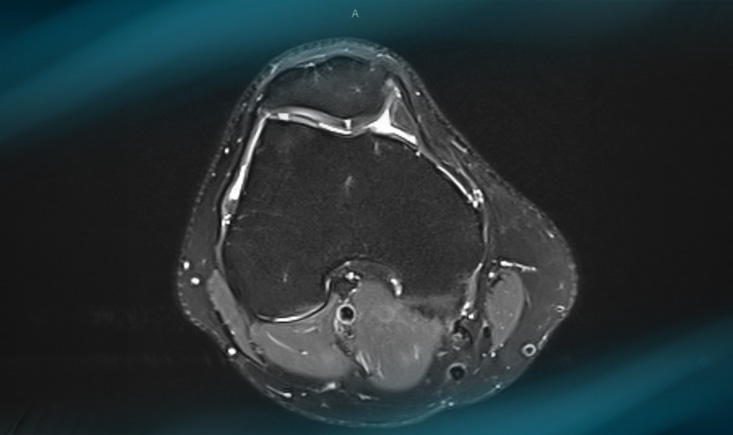

MRI